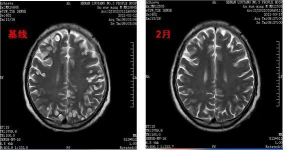

脑部肿瘤治疗前后对比